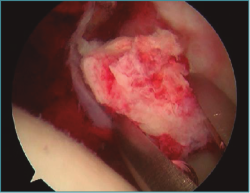

Se trata de un varón de 29 años que sufre una luxación posterior de cadera izquierda tras la caída de una lancha acuática de 1.600 kg sobre su miembro inferior. Se trata mediante reducción cerrada de cadera dentro de las 6 primeras horas posteriores a la luxación. La reducción fue satisfactoria, pero la TC muestra la presencia de fragmentos intraarticulares (Figura 1). Se le realizó tratamiento artroscópico de cadera con extracción de fragmentos (Figura 2).

Figura 2. Fragmento óseo intraarticular extraído mediante artroscopia.